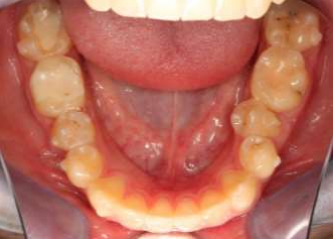

Fig. 2: Fit problems in region 35

Fig. 3: Fixing braces of tooth 36-34 to straighten tooth 35 more quickly